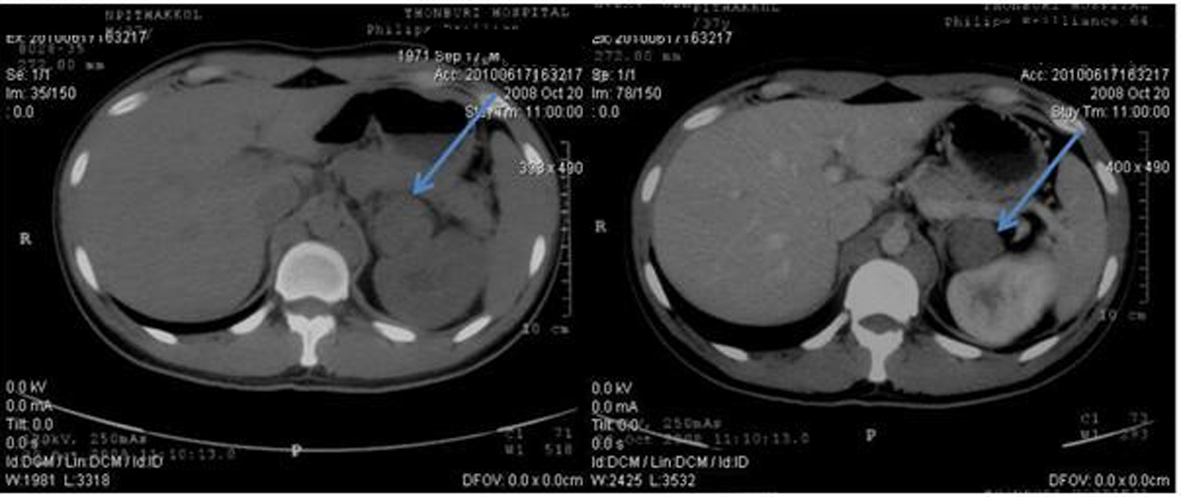

In October 2008, a 37-year-old previously healthy Thai male, with 3cm left supraclavicular lymph node enlargement. The lymph node was biopsied and sent to pathologist and the result showed metastatic well differentiated adenocarcinoma. CT chest and abdomen was done to search for the primary site. It revealed mildly reticular densities at right lung apex, malignant lobulated heterogeneous soft tissue mass at left neck extending downward to level of the aortic arch. Direct tumor invasion was seen at left common carotid and subclavian arteries and left lobe of thyroid gland and partially abuts wall of esophagus. Left paraaortic multi-lobulated nodes were enlarged at the renal level. The mass displaced the left renal vein anteriorly. Some mass effect was noted with mildly dilated left renal pelvis. The 7.4 cm lesion partially abutted wall the aorta and body of the pancreas (Fig. 1-3).Tumor markers including AFP, LDH and CEA were within normal limit.

![]() Click for large image | Figure 2. Pretreatment CT scan of abdomen in October 2008 (Pre-contrast on left side and post-contrast on right side) showing paraaortic lymph nodes enlargement on left side partially abuts wall of aorta and body of pancreas. |

![]() Click for large image | Figure 3. Pretreatment CT scan of abdomen in October 2008 (Pre-contrast on left side and post-contrast on right side) showing enlargement of multilobulated left paraaortic node at the renal level, 7.4 cm in size. The mass displaces the left renal vein anteriorly. Some mass effect is noted with mildly dilated left renal pelvis. |